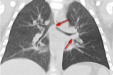

一岁多小孩被碎骨头堵气道险酿悲剧,医生提醒……